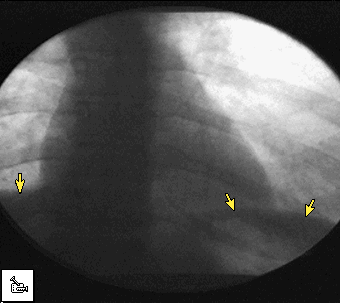

| fluoroscopy | term type: main entry term number: singular reliability code: 10 definition: diagnostic X ray procedure in which the X ray is projected onto a screen. Because this procedure is a continuous X ray, it shows the movement of the internal organs. However, there is greater exposure to radiation than in a conventional X ray. (en) check date: 09/08/2001part of speech: other context (x): I_fluscp.txt originator: Arianne |